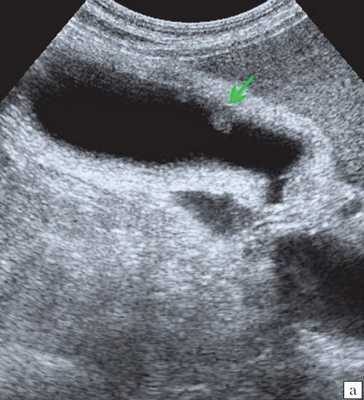

- УЗИ желчного пузыря. Эхогенная картина не слишком специфична и достаточно изменчива. На мониторе можно увидеть изменение структуры, толщины стенок, значительное увеличение объема пузыря. Внутри органа визуализируется скопление желчи, возможно с газовыми пузырьками, неоднородным осадком, хлопьями. В перипузырном пространстве обнаруживается выпот и скопление жидкости.